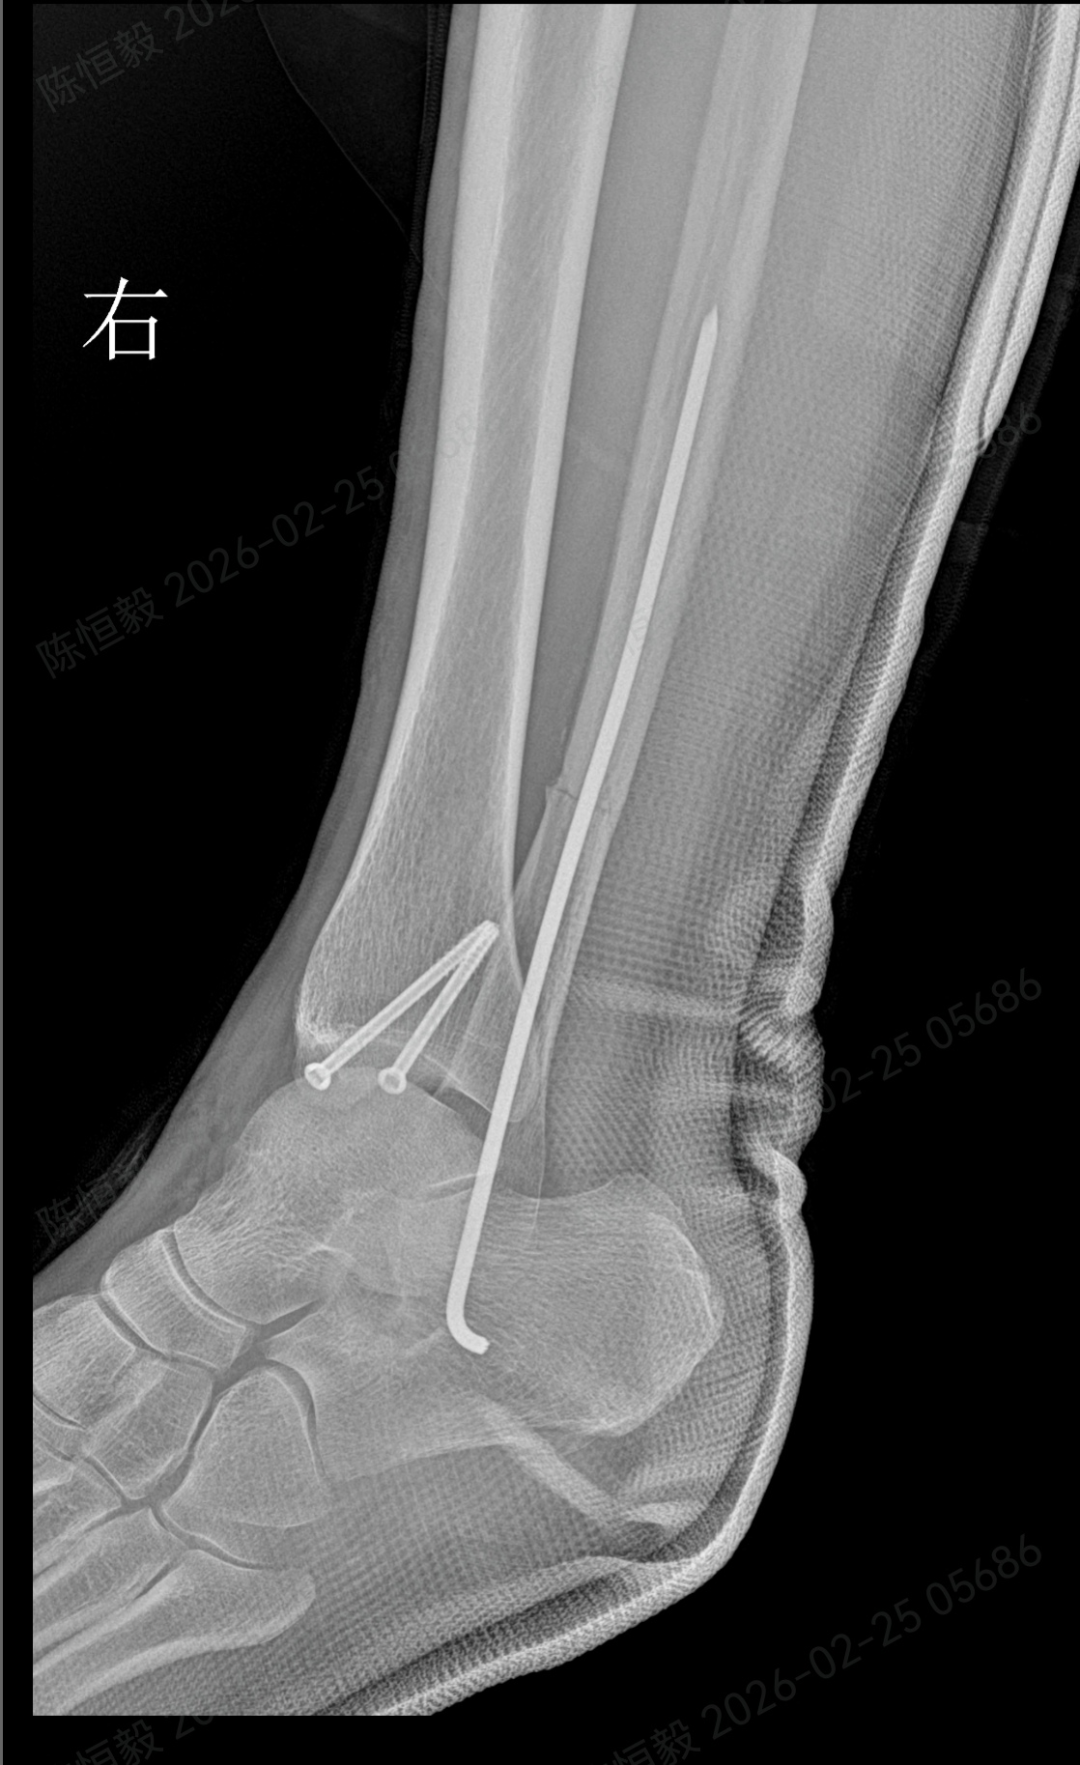

针对王女士的踝关节骨折情况,由副主任医师陈涛主刀,足踝外科团队为其实施了关节镜辅助下机器人导航微创闭合复位内固定术。

依托机器人导航系统,规划螺钉置入通道,避开关节面与重要组织;

最后通过另外两个 5 毫米的小孔置入空心螺钉,完成骨折端的稳定固定。

整个手术仅通过三个 5 毫米的小切口完成,最大程度降低了手术创伤。

术后的恢复情况也契合了王女士的期待:

术后第二天,王女士便可在床上进行踝泵训练;

术后第三天,在充气靴保护下能够部分负重行走;

术后两周复查,手术切口愈合状况良好,几乎无明显痕迹。